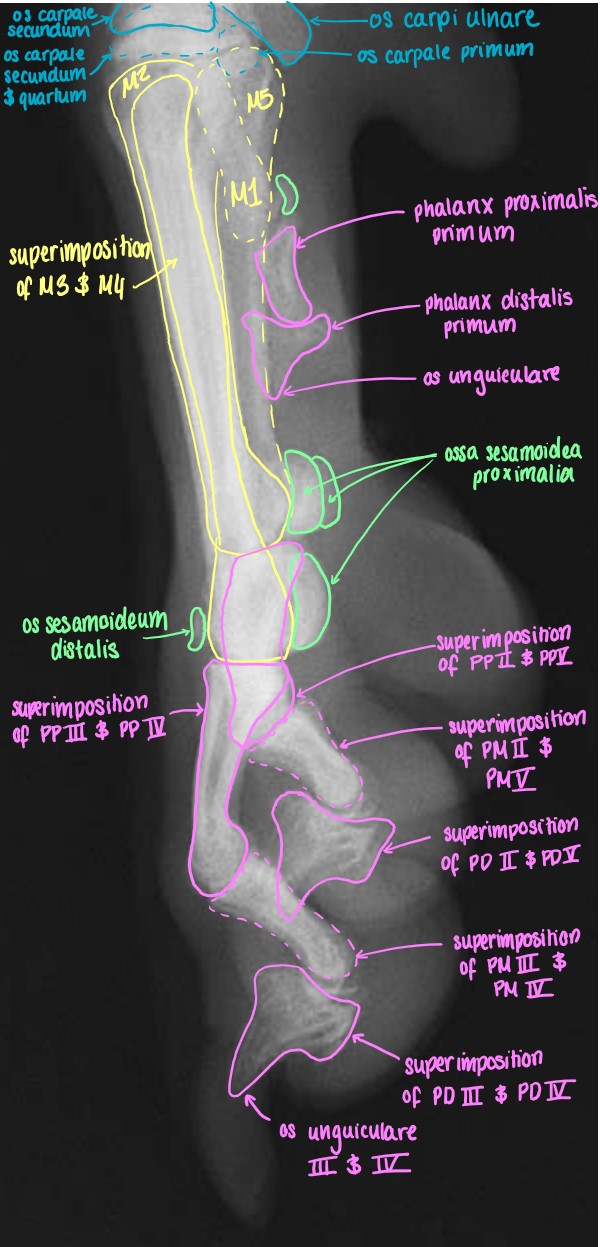

Manus